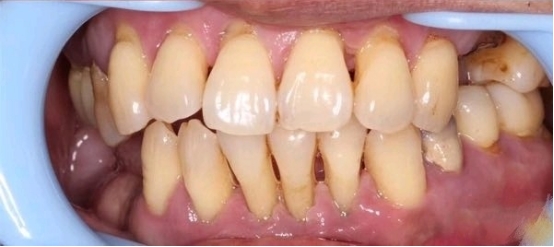

重度牙周炎的示意图

牙周病导致牙龈萎缩、牙根暴露,甚至牙齿松动

经过牙周治疗以后,牙周炎得以控制